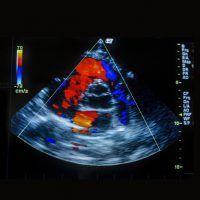

Echocardiogram (Echo)

An echo is an ultrasound scan of the heart. The test is used to acquire images of the heart, to identify if the heart is pumping effectively, if there’s a valve abnormality, or if there’s any previous damage to the heart.

Insurance: check with your provider

Procedure code: 5108